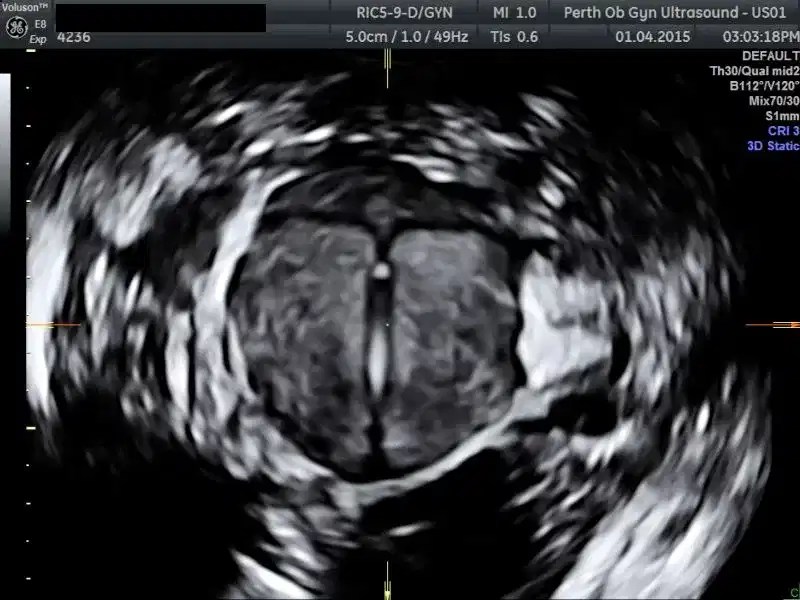

From www.volusonclub.net

The Role of 3D Ultrasound in Pelvic Reconstruction Surgery Empowered What Is A 3D Pelvic Ultrasound A pelvic ultrasound is an imaging test that uses sound waves to make pictures of what's inside your pelvis. It provides detailed views for. A pelvic ultrasound is a diagnostic exam that produces images—which are called sonograms—of the organs and structures within the pelvis. A pelvic 3d ultrasound includes a routine pelvic ultrasound with additional 3d views. What is a. What Is A 3D Pelvic Ultrasound.